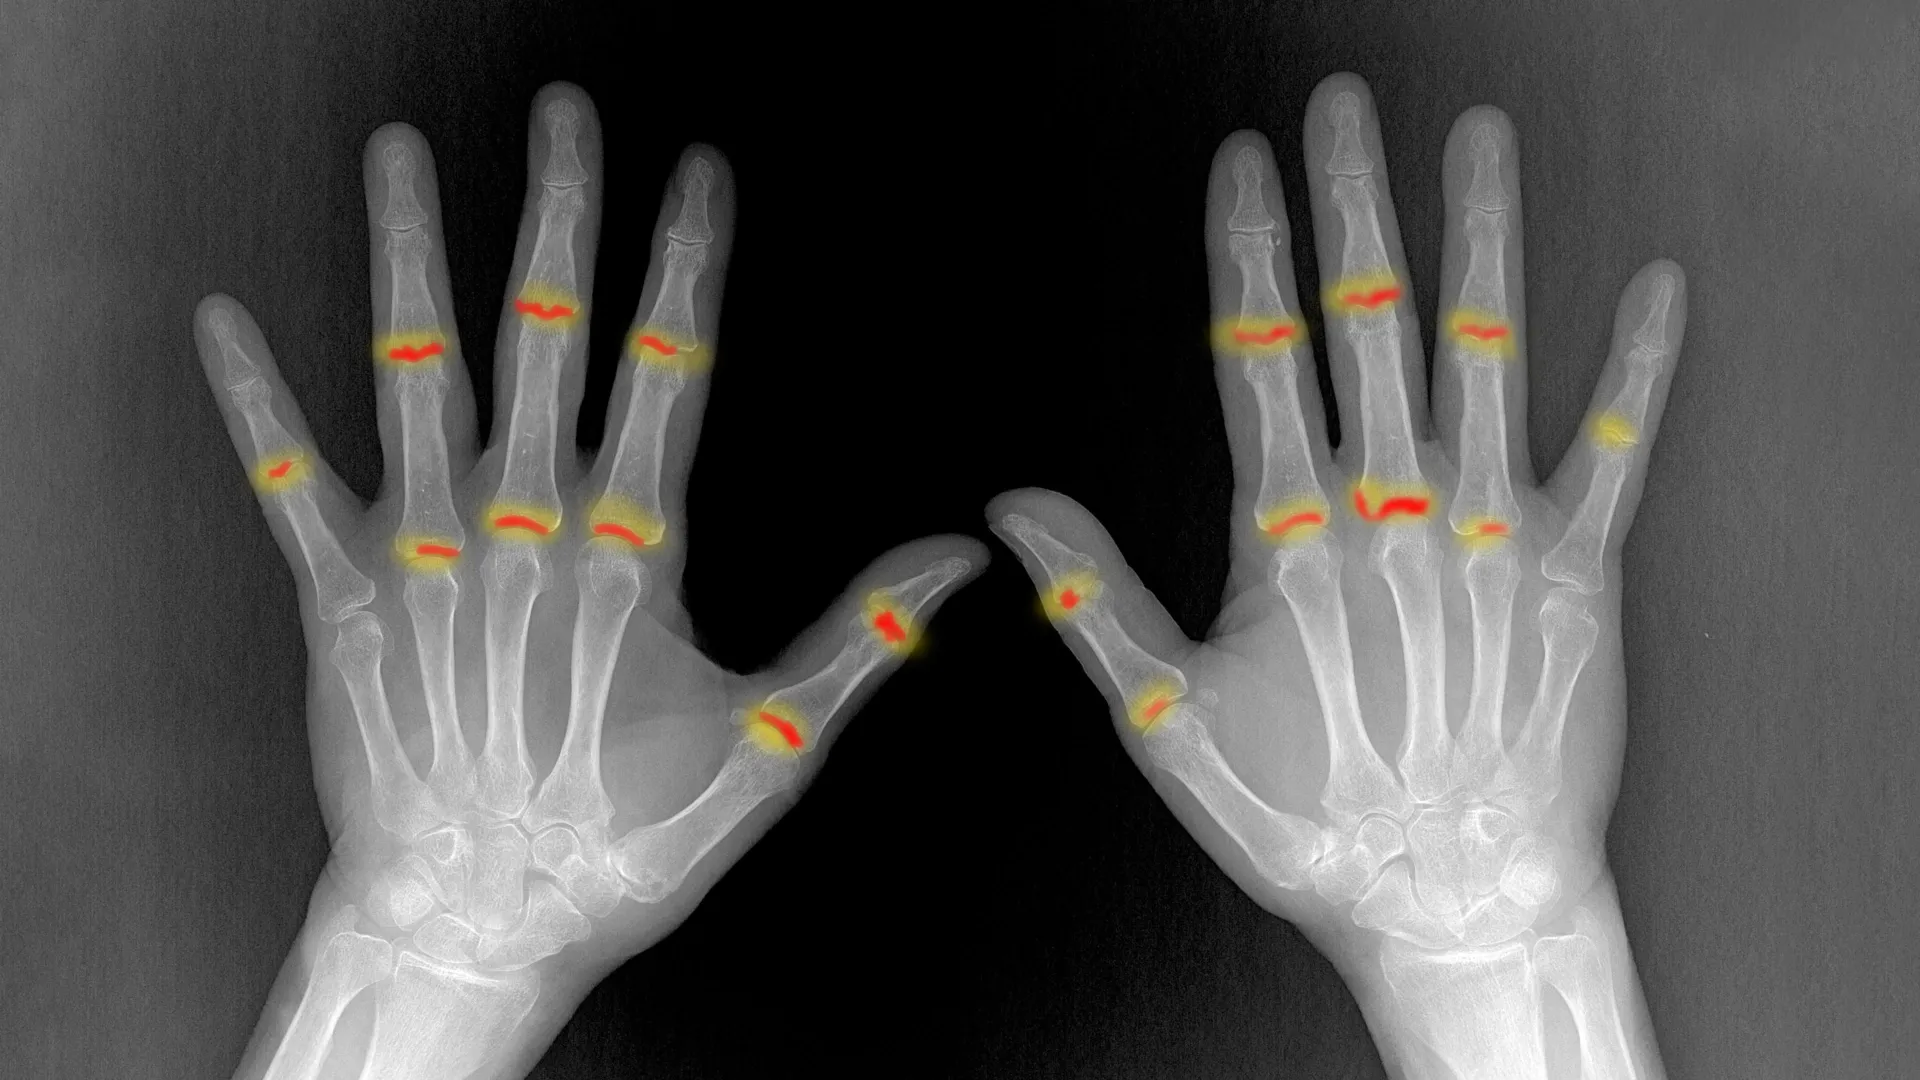

چرا پسوریازیس به مفاصل حمله میکند؟

محققان دانشگاه اورلانگن آلمان موفق شدند مکانیزم دقیق تبدیل پسوریازیس پوستی به آرتریت مفصلی را کشف کنند. آنها دریافتند که التهاب در پوست باعث ایجاد سلولهای ایمنی خاصی میشود که وارد جریان خون شده و به سمت مفاصل سفر میکنند. اما جالب است بدانید که صرف ورود این سلولها به مفصل باعث بیماری نمیشود؛ بلکه مشکل اصلی زمانی رخ میدهد که سیستم دفاعی طبیعی مفصل نتواند به درستی پاسخ دهد.

در افراد سالم، سلولهای بافتی به نام فیبروبلاست وظیفه محافظت از مفصل و کنترل سلولهای التهابی را بر عهده دارند. اما در بیمارانی که دچار آرتریت پسوریاتیک میشوند، این عملکرد محافظتی به شدت ضعیف شده و اجازه میدهد سلولهای مهاجر آتش التهاب را روشن کنند. این کشف توضیح میدهد چرا برخی بیماران پوستی دچار آسیب مفصلی میشوند و برخی دیگر نه.

این یافتهها که در مجله معتبر Nature Immunology منتشر شده، راه را برای تشخیص زودهنگام باز کرده است. اکنون محققان میتوانند این سلولهای مهاجر را در خون بیماران شناسایی کنند، حتی قبل از اینکه علائم مفصلی ظاهر شود. این پیشرفت به توسعه درمانهای جدید کمک میکند تا بتوان با هدف قرار دادن این سلولها، از بروز آسیب دائمی به مفاصل پیشگیری کرد و رویکرد پزشکی را از درمان به پیشگیری تغییر داد.